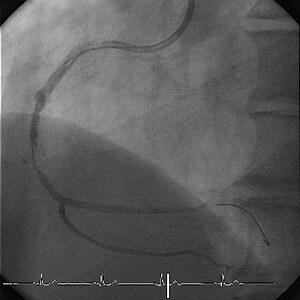

半年前に#12のAMIでPCIしましたが、その際にRCAが根っこからCTOとなっておりました

(Fig.1)。

これに対してはNIRのdist.にTsunami 3.0×30mm(Fig.2)、NIRのprox.にDuraflex

3.5×18mmを留置いたしました。

その際に血栓がモクモク沸いてきて何度かballooningしてbailoutしています(Fig.4)。

一応、念のために2ヶ月後に確認したところ綺麗でした(Fig.5)。

6ヵ月後の確認では#2のTsunami内に50%狭窄を認める程度でした(Fig.6,7)。

カテしてみると(Fig.8)のようになってました。

aspirationカテで引いてみるとstent留置部全長にわたり血栓を認めました。

aspiration後の造影です。

dist.もステント外はきれいですのでやはりステント内のeventではないかと思います。

50%狭窄の部分がやはり狭窄として残っています。

#1dist.にはやや広い場所がありますが・・・

まだまだ吸いきれていない壁在血栓が残存しているでしょうからなんとも言いがたいで

す。